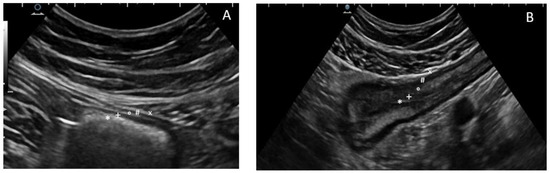

3.3. Transperineal Ultrasound